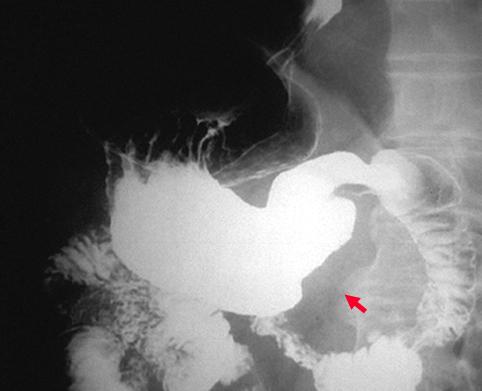

Criteria of Hist.ClassificationMalignant epithelial tumor/Undifferentiated carcinoma

LocationStomach/Antrum

Technique, MethodX-ray

Macroscopic TypesType 2 Ulcerated type with clear margin/

Size40 -

Depth of Tumor Invasionserosa (adventitia)